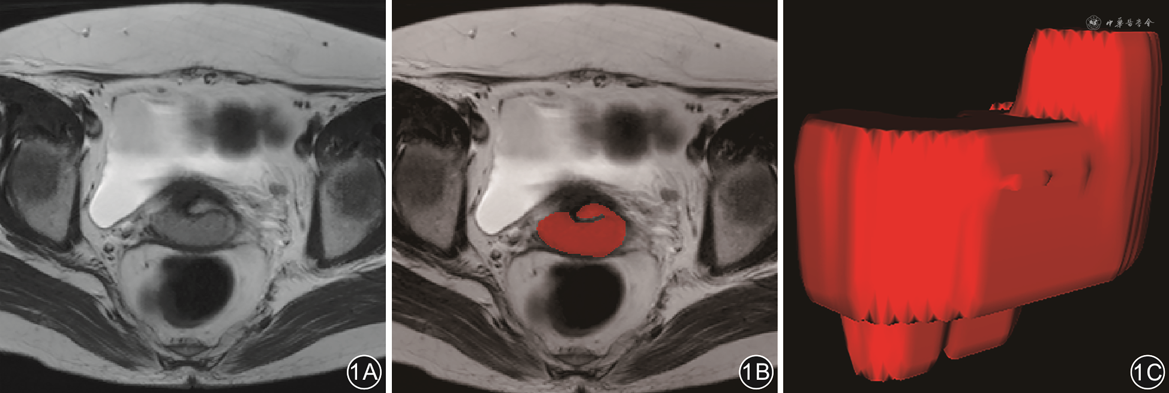

将横断位T2WI、DWI及cT1WI数据以DICOM格式导入ITK-SNAP(http://www.itksnap.org)软件,由1名具有10年工作经验的影像科医师逐层进行手动勾画肿瘤轮廓ROI(图1),得到三维感兴趣区(volume of interest,VOI),同时将DWI勾画的信息对应至ADC图上。勾画范围包括瘤内出血坏死区域。当肿瘤边界不清晰时,多个序列互相对比参照确定。如有分歧,与另1名有15年以上经验的影像科医师进行讨论确定勾画范围。以上勾画过程均在不知晓病理结果的前提下进行。